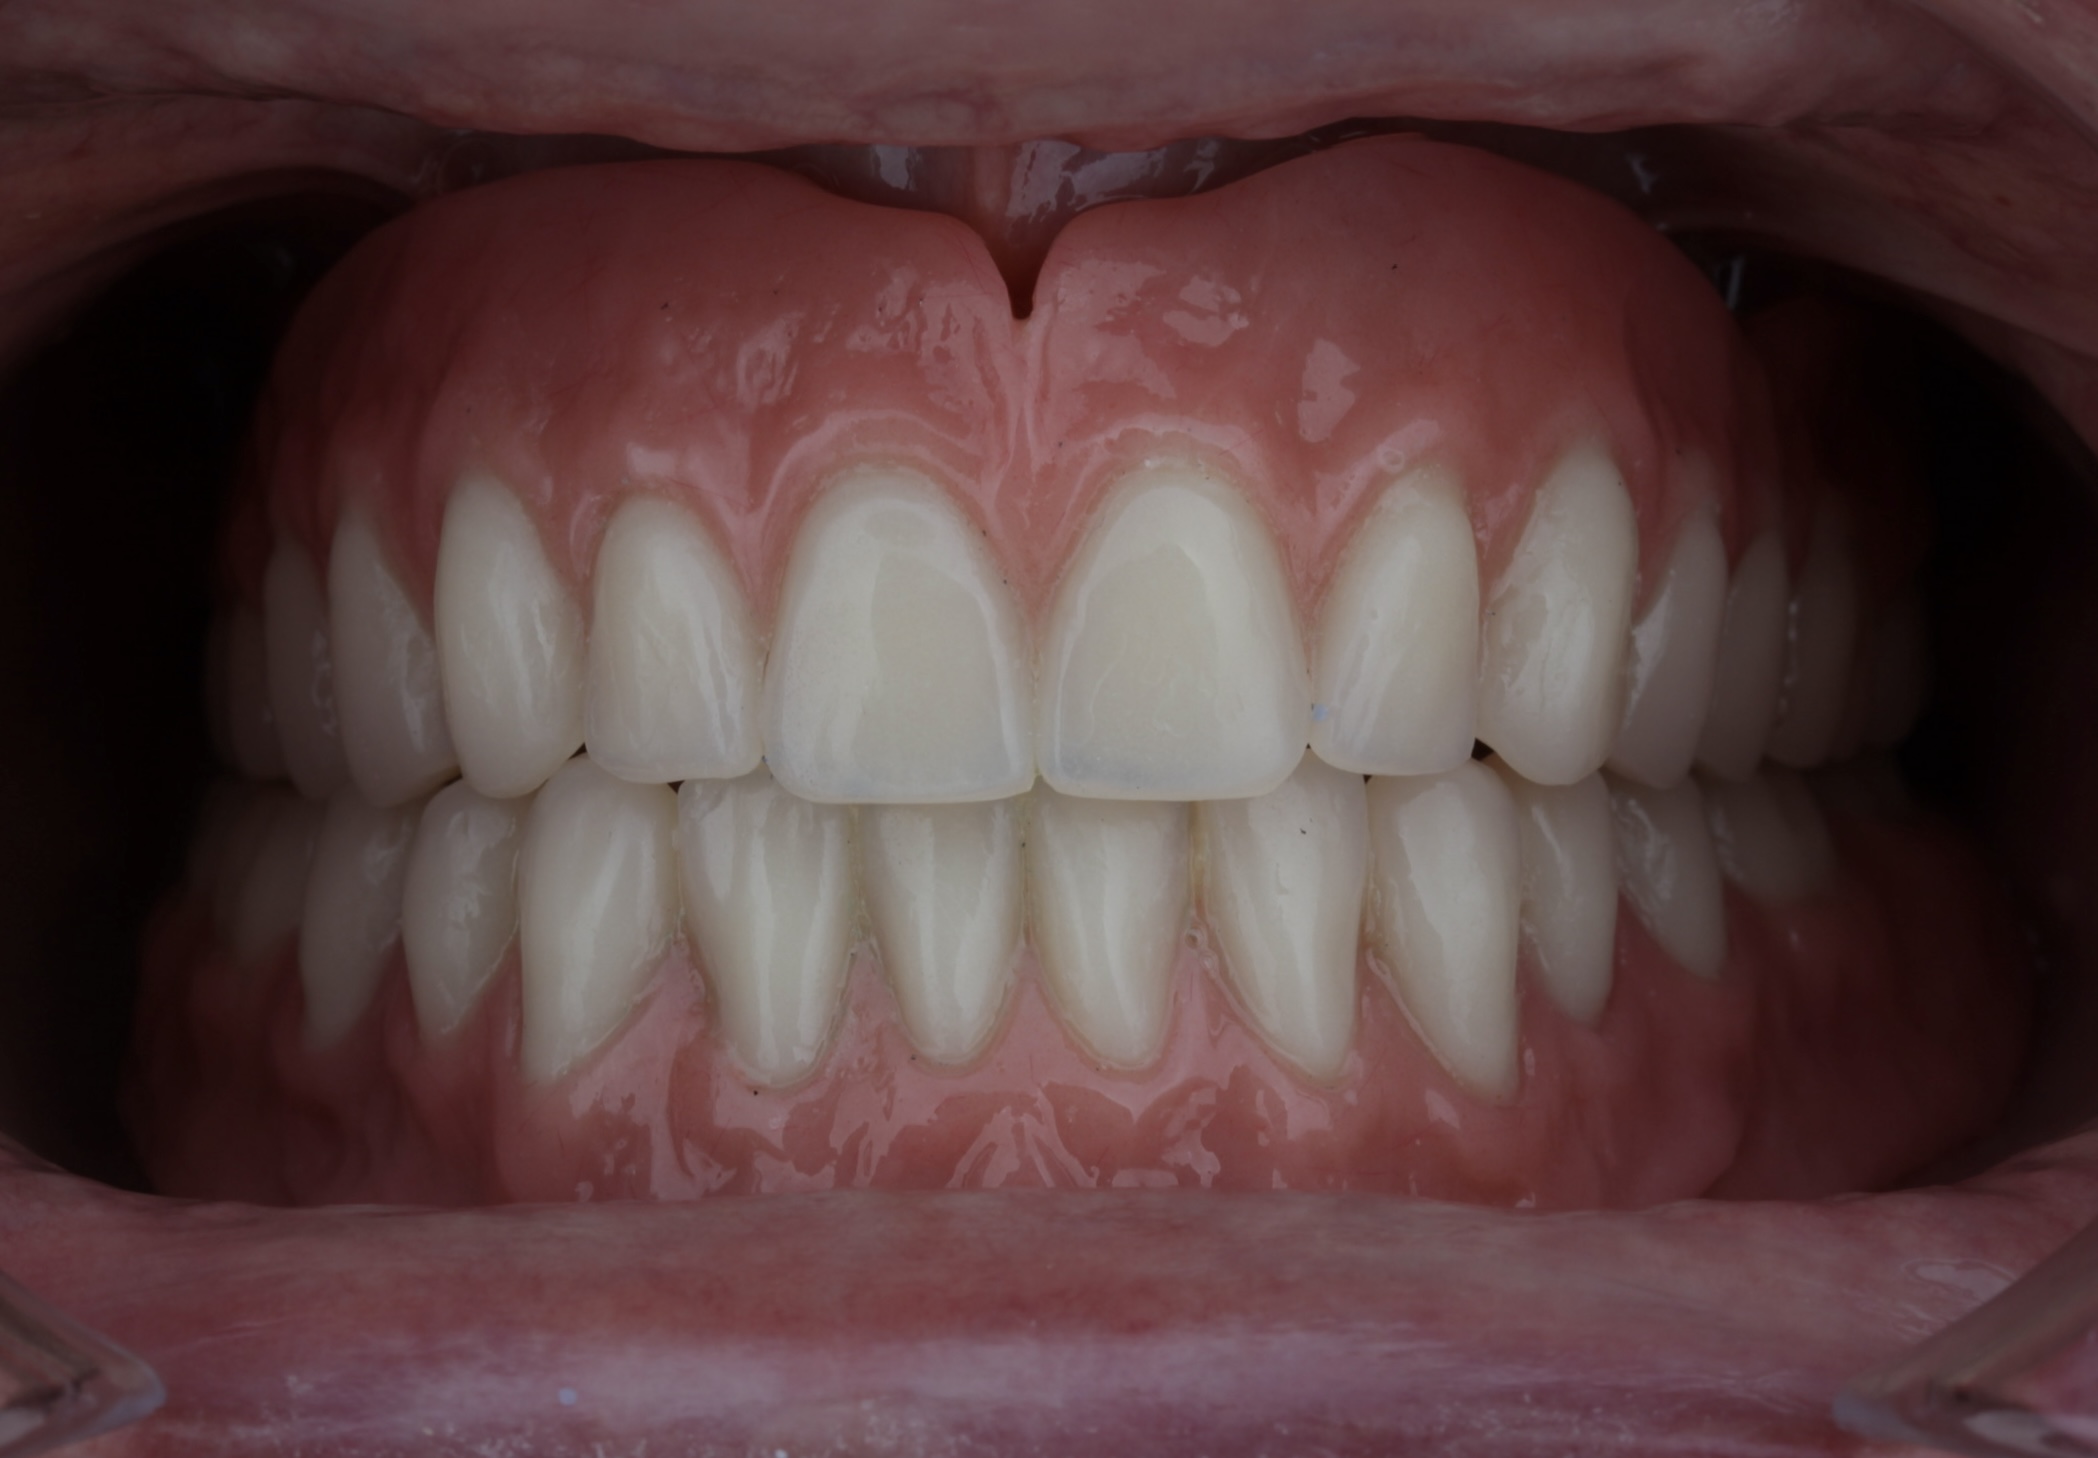

Coronas fijas en los 2 centrales.

En este caso la paciente llevaba unas coronas antiguas y se habian fracturado, se han realizado 2 coronas individuales .